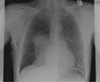

11

Q

A

Pneumothorax

How well did you know this?